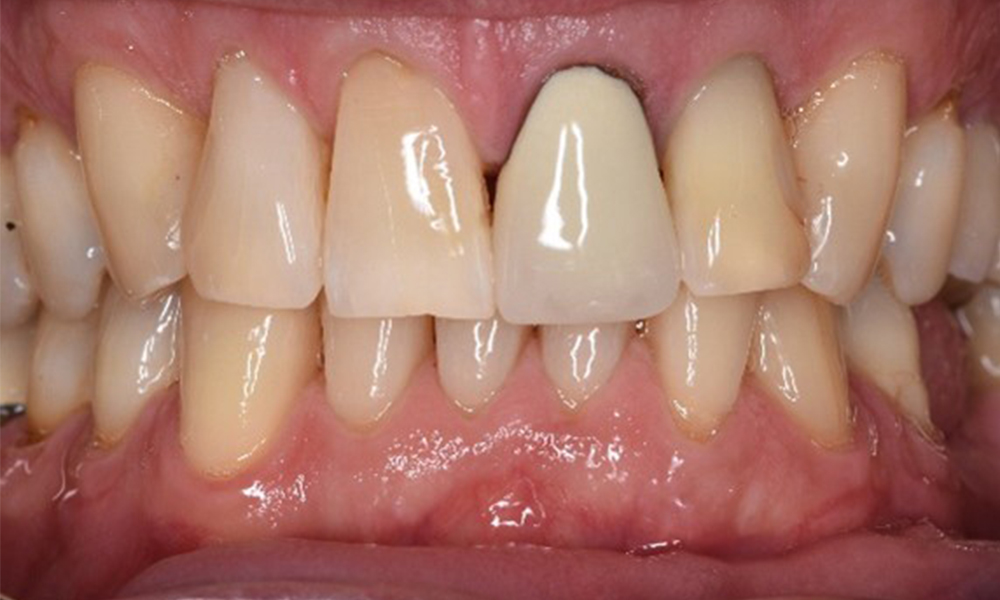

The transplant patient with gingival overgrowths

A 71-year old patient presents with having previously undergone a kidney transplant and with a history of hypertonia (high blood pressure). Due to his medical history, long-term medication with cyclosporine is required to suppress the immune system, as well as amlodipine to lower blood pressure. The patient also reports sensitive and bleeding gums. From an oral health perspective, the patient has undergone dental restoration and has eight missing teeth, pronounced gingival growth, and grade B, stage II periodontitis with active pockets and initial root caries on tooth 22. The caries risk assessment determines a moderate risk of caries (API 60). The following treatment recommendations can be determined for the prophylaxis session. more